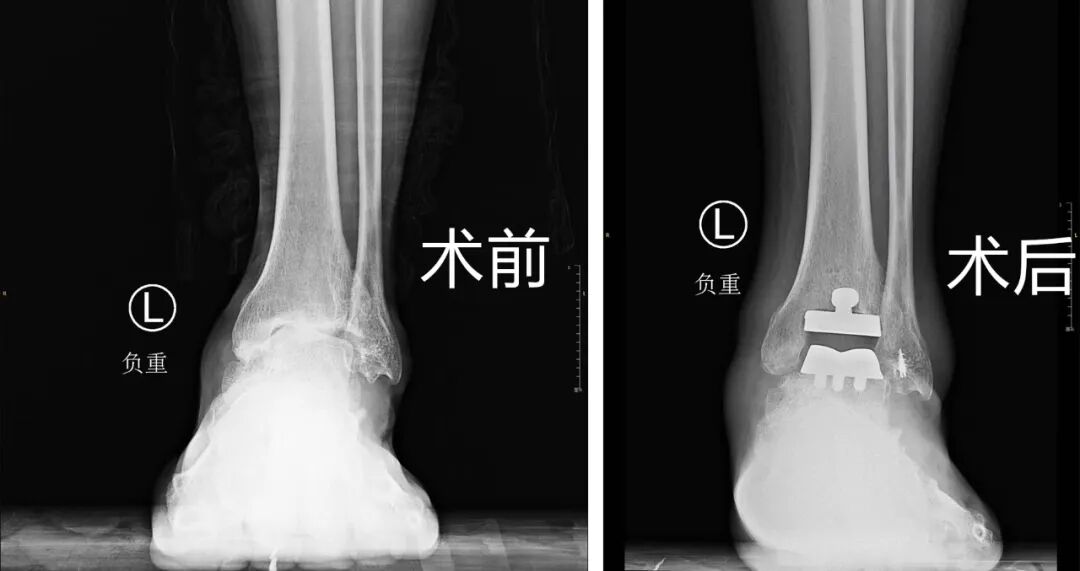

十多年前,赵大叔左脚崴了一次,疼了很久,但一直没有正规治疗过,也就敷敷膏药,休息几天,慢慢的踝关节状况越来越差,最后拖成了终末期踝关节炎。当时来院的时候赵大叔脚部情况很差,距骨坏死,外侧副韧带有陈旧的疤痕,踝关节的周围都是骨赘,而且软骨的损伤是比较重的,踝关节正常的关节面已经不存在了,每走一步都疼痛不已。

对于终末期踝关节炎,临床治疗有两种方法,一是关节融合,就是将关节固定,患者踝关节不能再曲伸,二是全踝关节置换,可以保留踝关节功能。经过沟通,大叔选择了可以保留踝关节活动的全踝关节置换术。

这次家访的时候,赵大叔通过锻炼已经具备了踝关节正常跖曲和背伸的功能,曹广超主任通过查体发现小腿肌肉力量仍有不足,后续还要通过锻炼来加强小腿肌肉的力量。